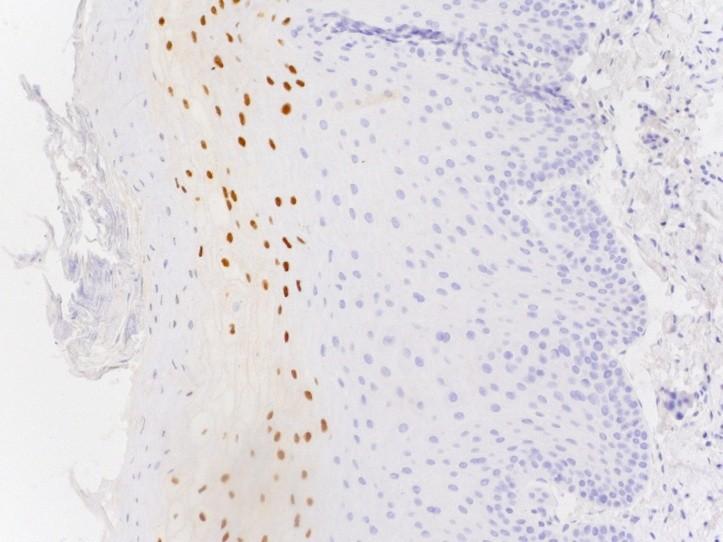

Molecular basis of HPV ca

Viral protein E6 inactivates p53

Viral protein E7 inactivates Rb

Rb normally held in a complex with E2F

E2F when free triggers cell cycle

Methods of testing

If positive HPV ISH or PCR (or both)